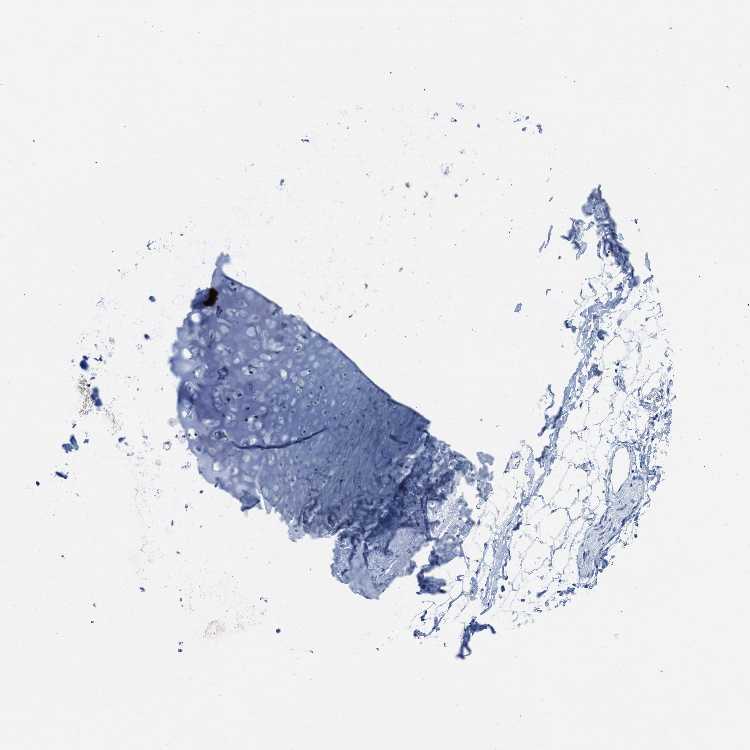

SOFT TISSUE 1 - Antibody stainingi

Antibody staining in the annotated cell types in the current human tissue is reported as not detected, low, medium, or high, based on conventional immunohistochemistry profiling in selected tissues. This score is based on the combination of the staining intensity and fraction of stained cells.

Each image is clickable and will lead to virtual microscopy that enables deeper exploration of all samples and also displays staining intensity scores, fraction scores and subcellular localization as well as patient and tissue information for each sample.

Antibody HPA017168

Chondrocytes Not detected

Fibroblasts Not detected

Peripheral nerve Low

SOFT TISSUE 2 - Antibody stainingi